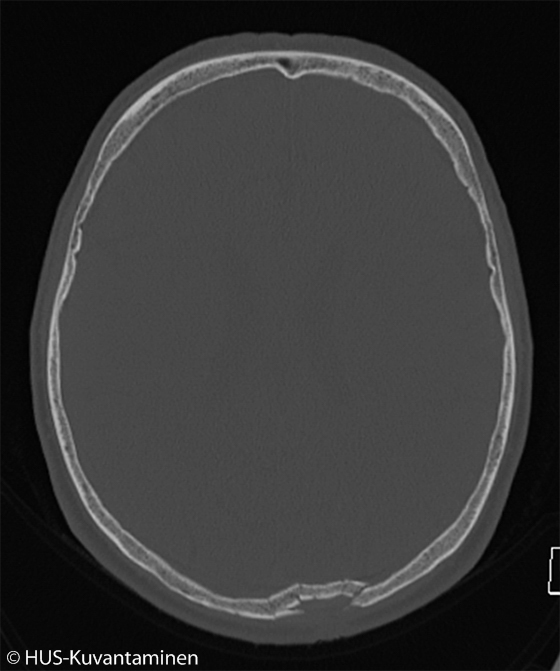

Kallonmurtuma pään TT-kuvassa (kuva 1 ilman löydösmerkintöjä)

Mies löi kaatuessaan päänsä katukiveykseen ja menetti muistinsa useaksi tunniksi.